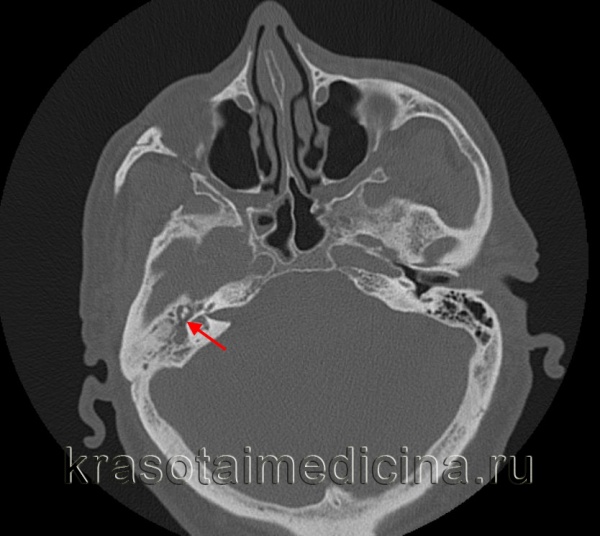

- Рентгенография, КТ височных костей. С целью оценки распространенности деструкции костных тканей и проведения дифференциальной диагностики назначается рентгенография височной области по Шюллеру и Майеру. При низкой информативности полученных рентгенограмм показана компьютерная томография височных костей в аксиальных и коронарных проекциях с шагом в 1-2 мм.

- Лучевые методы исследования. Обычно используется КТ височных костей, позволяющее визуализировать поражение слизистых оболочек среднего уха, формирование рубцов возле слуховых косточек, расплавление длинной ножки или тела наковальни, суперструктур стремени. При развитии осложнений происходит деформация и деструкция стенок крыши барабанной полости или пещеры, канала лицевого нерва и формирование фистул лабиринта. Реже применяется МРТ височных костей для детальной диагностики холестеатомного процесса и его дифференциации с другими патологическими изменениями.